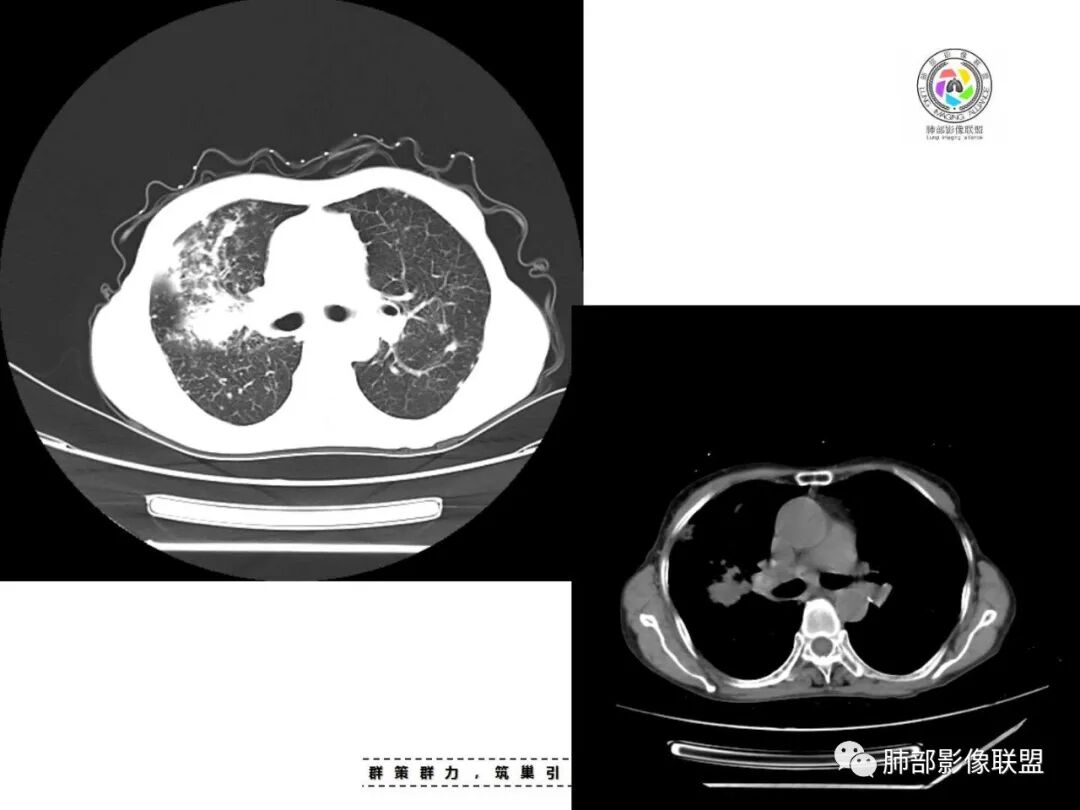

双肺多发片状影,索条影及小结节影,并见少许钙化,右肺上叶为主,主病灶无彭隆,考虑结核可能大

双肺不均匀散在分布斑片状,条索状,斑点状影,边缘部分清晰,可见部分病灶钙化,考虑感染性病变,结核?NTM?详细询问病史,尘肺+结核?

双上肺多发片状、索条影及小结节影,并见少许钙化,右肺上叶后段肿块,后段支气管阻塞,边缘膨隆,双上肺小叶间隔增厚呈多发结节状,胸膜局限性增厚,考虑:1、双肺上叶结核;2、右肺上叶后段腺癌并癌淋。

老年女性,短病程,咳嗽,咳痰为主诉,双肺多发病灶,右上为主,实变,小结节,条索,考虑结核,但小叶间隔增厚,胸膜下多发结节,警惕肿瘤。

女,67,咳嗽咳痰半月,双肺多发病灶,部分钙化,右肺为著,右肺上叶大片实变影,累及胸膜,右肺上叶支气管堵塞,右侧肺门略增大,考虑肺癌,双肺结核。

老年女性,主病灶在右肺上叶,有点散,周围可见卫星灶及少许树芽,双肺多发索条、结节及散在钙化,纵隔及肺门见钙化淋巴结,考虑结核。

双肺多发斑片,索条及结节影,内可见钙化,右肺上叶后段支气管截断,断端圆钝略扩张,双肺门及纵膈淋巴结钙化,双侧胸膜增厚伴钙化。首先考虑结核。右肺上叶亚段气管分叉处结节,警惕肿瘤

老年女性,双肺索条纤维影,右肺上叶散在卫星灶,树芽征,小叶中心融合,右肺后段支气管圆形截断,实变病灶内支气管扩张,考虑结核。

老年女性,病史半个月,两肺上叶为主病灶,多发不规则实变影、条索状影及散在小结节影,首先考虑结核,警惕合并肺癌,尤其是右肺上叶团块实变影。还可以看看重建图像,必要的增强。

患者老年女性,咳嗽、咳痰半月余。查体双肺可闻及痰鸣音。胸部CT:双肺上叶可见多发结节、条索、斑片实变影及小叶间隔增厚,部分见分叶、长毛刺及钙化,表面光滑,纵隔淋巴结有钙化。综合考虑良性病变,结核可能大,鉴别腺癌并癌性淋巴管炎。

老年女性,咳嗽咳痰,双肺散在片状及索条状高密度影,以右肺上叶为主,周围可见结节,实变内可见钙化,纵膈及双肺门可见钙化淋巴结,首先考虑感染性病变,结核可能大,警惕右肺上叶肿瘤并癌性淋巴管炎

双肺多发斑片,索条及结节影,内可见钙化,右肺上叶结节影,空泡,右肺上叶后段支气管截断,断端圆钝略扩张,双肺门及纵隔淋巴结钙化,双侧胸膜增厚伴钙化。首先结核肯定会有,右肺上叶结节,考虑腺癌

老年女性,咳嗽咳痰半月,肺部听诊痰鸣音。影像以右上肺实变?肿块?与支气管关系不清晰;另见两上肺结节、条索,胸膜局部增厚有钙化点,纵隔肺门淋巴结见钙化。综合考虑结核可能性大,注意肺癌。完善增强及支气管镜等检查。

老年女性,咳嗽咳痰半月,双上肺多发条索影,结节影,密度较高,右肺上叶不规则肿块,内有钙化,靠近胸膜下,靠内侧可见斑片影,树芽征,支气管壁增厚,考虑尘肺并肺结核,肺癌待排。

双肺上叶,结节,斑片,条索,大片实变影,支气管远端不通,是不是层面不够啊,后段支气管堵没堵?肺门纵隔淋巴结钙化,常规考虑结核。

双上肺索条,多发边缘清楚的结节,右上肺结节灶,无连续层面,不能判断支气管是否堵塞,双肺多发钙化,考虑结核,建议气管镜

常规考虑结核(鉴别尘肺合并结核,职业史?),老年人还要排除恶性(原发肺癌或者转移,需要结合病史与肿瘤标志物,必要时穿刺活检或支气管镜检)

双肺多发条索状,结节病灶,以右肺显著,部分病灶有爬树征,树芽征,未见明显钙化,纵隔淋巴结增大钙化,常规考虑结核,不能排除肺癌,建议增强和支气管镜检查

两肺上叶多发索片小结节影,部分密度较高,中央间质和周围间质都增厚,肺门纵隔淋巴结肿大钙化,基础疾病考虑有尘肺或陈旧结核,需结合相关病史;右肺上叶见斑片点片状模糊影,部分树芽征上叶后段局部细支气管闭塞,考虑感染,结核可能性大,右肺上叶后段病灶实变成团块状,密度低于胸壁肌肉,首先还是考虑结核肉芽肿,治疗后复查除外合并肿瘤可能。

老年女性,67岁,咳嗽、咳痰半月余。双肺可闻及痰鸣音。

胸部CT:双肺上叶多发小结节,沿胸膜下、支气管血管束分布。右上肺斑片实变影、索条影及小叶间隔不均匀增厚,支气管枯枝征?纵隔淋巴结多发肿大,部分有钙化。综合考虑:结节病?尘肺?鉴别:腺癌并癌淋。

1.双肺片状影、大小不等斑片影、结节影、树芽等,病灶密度偏高多钙化。

2.病灶上肺为主,胸膜下分布为主。双肺病灶明显不对称,右肺块状影较大。

3.纤维条索影广泛杂乱、牵拉,横向分布为主,这点给人也印象很深!

4.纵隔轻度右移。双肺门纵隔淋巴结增大钙化。

5.老年女性患者,咳嗽咳痰半月余